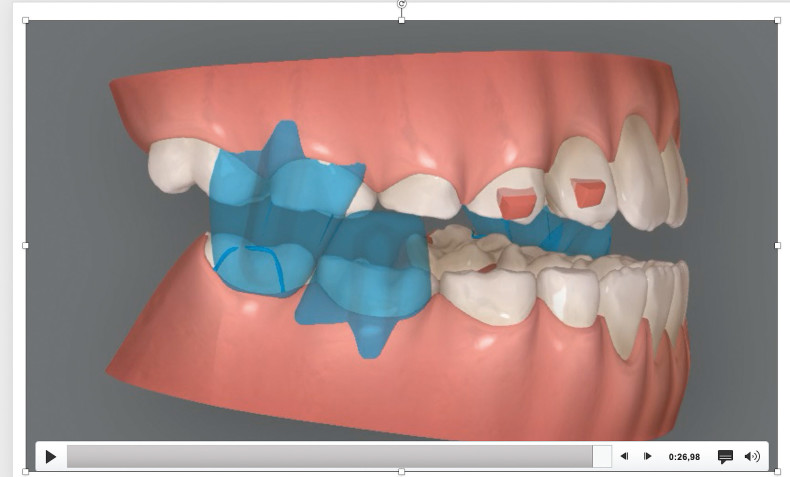

Klinisches Fallbeispiel 2 (Abb. 2a–y)

Distalbiss und tiefer Biss bei einem zwölfjährigen Mädchen. Die Behandlung erfolgte mit Invisalign und Precision Wings. Insgesamt waren zwei Schienensätze notwendig. Die Gesamtbehandlung dauerte 18 Monate.Bei der Planung des ClinCheck wurde der tiefe Biss vorwiegend über eine Intrusion der Unterkieferfront behoben, um die Lachlinie der Patientin nicht negativ zu beeinflussen. Die Oberkieferfront wurde nur retrudiert, jedoch vertikal nicht intrudiert. Während der Phase des Mandibular Advancement wurde die Wirkung der Precision Wings durch den Einsatz von Klasse II-Gummizügen unterstützt. Schlussendlich wurde auch der hängenden Okklusionsebene durch eine einseitige Intrusion der Molaren im ersten Quadranten Rechnung getragen.